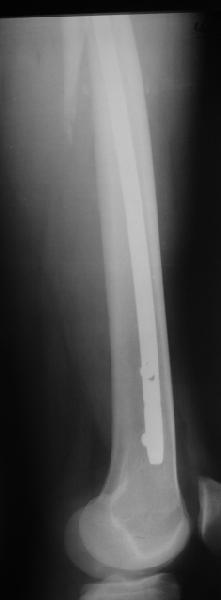

Да, сейчас это и у нас самый напрашивающийся выбор. Сделали гвоздем ChM, картинки в приложении.